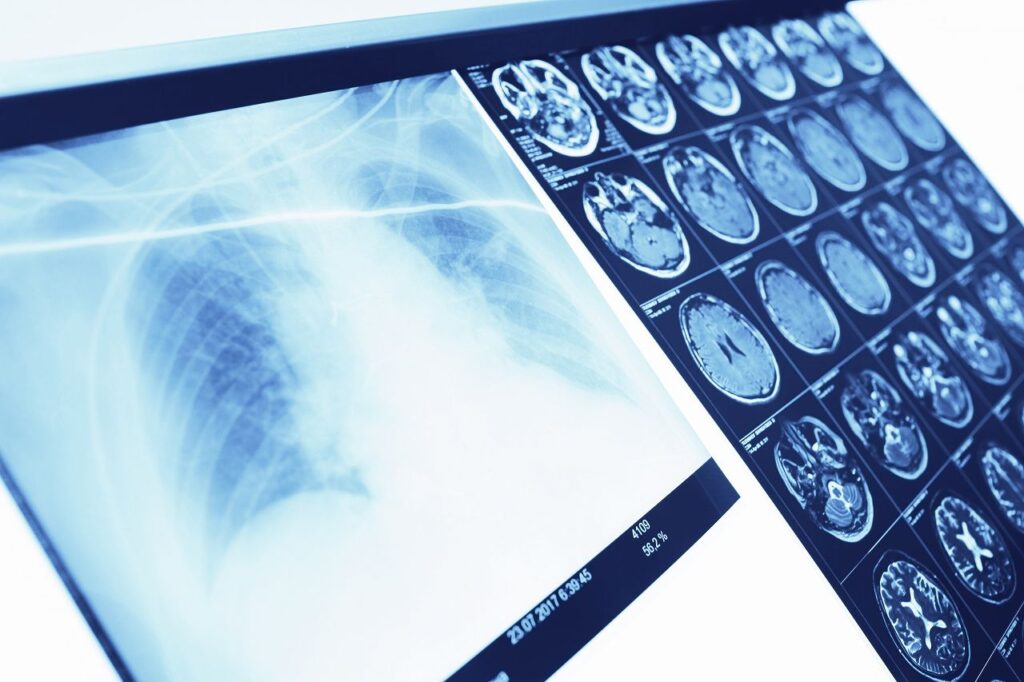

体の中を「見て調べる」検査を行っています

画像診断部では、

レントゲン、CT、内視鏡などの検査を通して、体の中の状態を詳しく調べる診療を行っています。